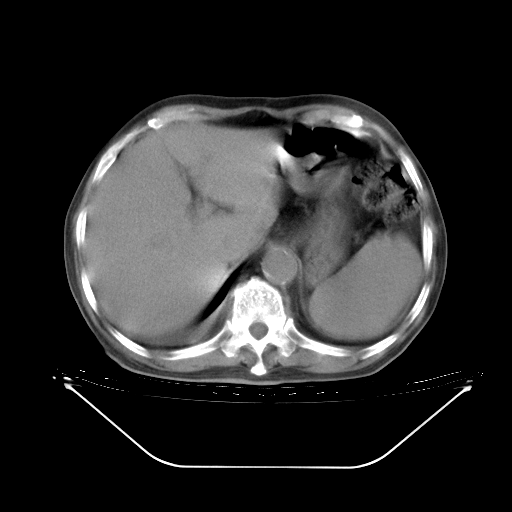

胸腹部CT,诊断意见:左上肺叶钙化灶、左侧胸膜局限性增厚并钙化、胆囊炎。描述部分肺组织呈磨玻璃样改变。

今天复查肺部CT,发现双肺广泛磨玻璃样改变。所以我把3月19日和5月9日相隔50天的肺部CT上传。请大家会诊。

5月9日肺部CT(在4月27日齐鲁医院肺部CT描述部分肺组织磨玻璃样改变,12天后肺组织广泛磨玻璃样改变)

2009年5月9日肺部CT

大致读了系列胸部CT:纵隔窗无明显异常,肺窗:从4、27至今:主要是双肺中下野外带可见毛玻璃样改变,目前处于急性肺泡炎阶段,至于原因考虑1、结替组织或胶原血管性疾病所致?2、恶性疾病如恶组在肺部所致的表现或细支气管肺泡癌?3、药物或其它原因如肺蛋白沉着症所致肺泡炎目前不太可能?总之,明天就去请我院的呼吸科、感染科、血液科和临免专家会诊哈。